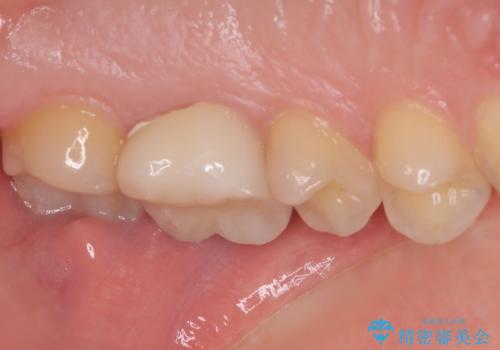

- 奥歯の銀歯の下にあるむし歯治療を希望して来院された患者様です。

口を開けたときに見えてしまう部分はセラミックインレーやジルコニアクラウンに、目立たない部分はゴールドインレーにてむし歯治療を行うこととしました。

機能面を優先すると、PGAインレー(ゴールドインレー)による修復治療やPGAクラウンによる補綴治療が望ましいのですが、笑ったときに見えている銀歯がどうしても気なってしまうとのことで、目立ってしまう奥歯はセラミックインレーやセラミッククラウンを装着することとしました。

見た目を気にすることなくむし歯治療を行うことができ、患者様に大変満足していただきました。